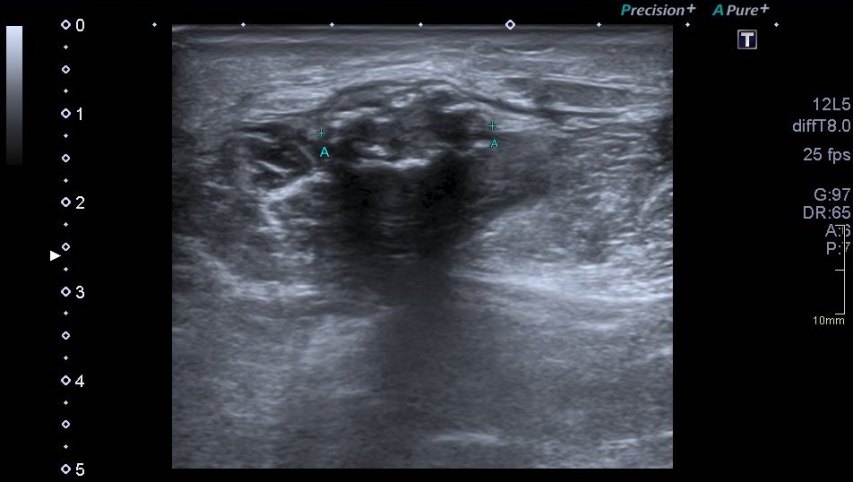

Lo primero que hay que hacer es ir a la zona de interés y comprobar que toda la ecoarquitectura es correcta, en la primera visulización observo una imagen que me llama poderosamente la atención (fig 1).

Se objetiva un Recto Anterior aumentado de tamaño, heterogéneo y romo, sin continuidad, el Crural normal, profundo, ecográficamente sin cambios.Lo indica la flecha amarilla.

Me deslizo por la cara anterior a buscar la inserción del recto anterior en la rótula, observando que entre la zona de discontinuidad y la rótula, no existe presencia del Recto Anterior, aunque el Crural inserta en su localización. En el trayecto que debiera estar ocupado por el Recto Anterior solo hay una mínima cantidad de líquido filiforme,un hematoma en evolución apoyado sobre la fascia que separa el teórico lugar del Recto Anterior y el Crural, alargado e hipoecogénico lo que supone una lesión no aguda. (Fig. 2)